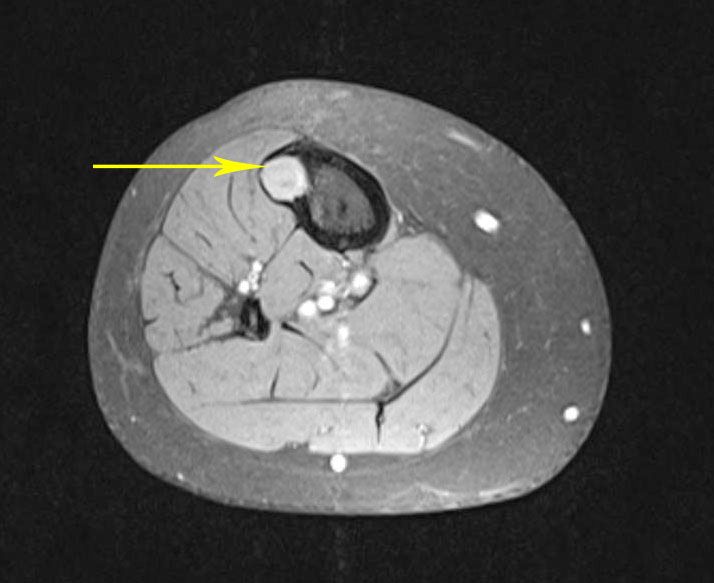

En esta TC transversal de tibia, se puede ver con claridad un tumor óseo en color blanco brillante en comparación con el color más oscuro del hueso.

Es posible que necesite una TC si tiene un problema con una estructura ósea pequeña o si tiene un traumatismo grave en el cerebro, la médula espinal, el pecho, el abdomen o la pelvis. A veces, le pueden administrar un tinte o un material de contraste para que determinadas partes del cuerpo se muestren mejor.